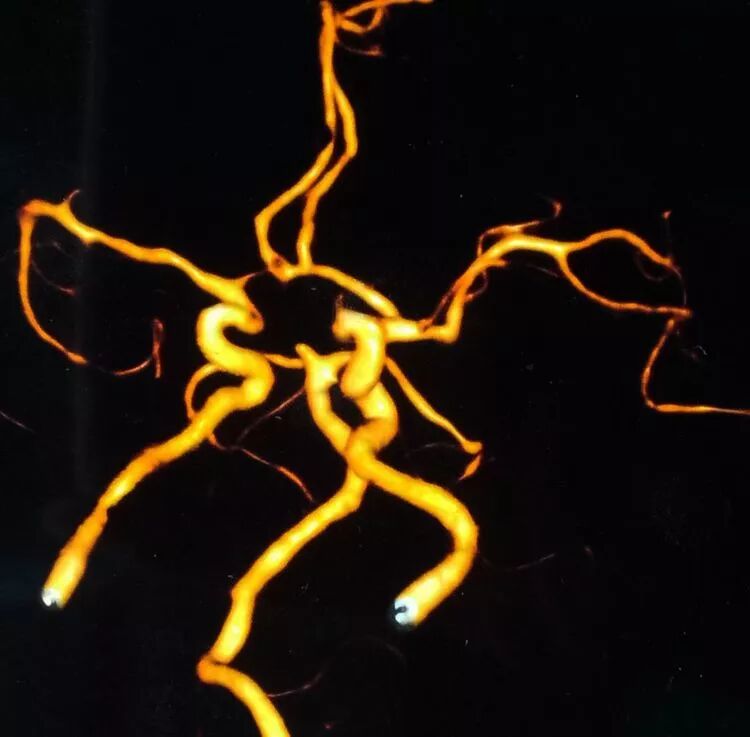

基底动脉顶端微小动脉瘤,是个有欺骗性的病例。从下面这个角度的造影看,瘤体长轴跟基底动脉主干平行,似乎用直头微导管栓塞即可

但从侧位造影和CTA观察,其实瘤体长轴还是跟基底动脉主干有成角的。这家医院的DSA机器没有三维重建工作站,只能参考CTA

于是我们把微导管头塑成S形

顺利完成该动脉瘤的栓塞。所以,要多角度观察动脉瘤跟载瘤动脉的解剖走行,即使硬件上没有三维工作站,咱们头脑中也要有立体构象,不要一叶障目,被狡猾的敌人所欺骗